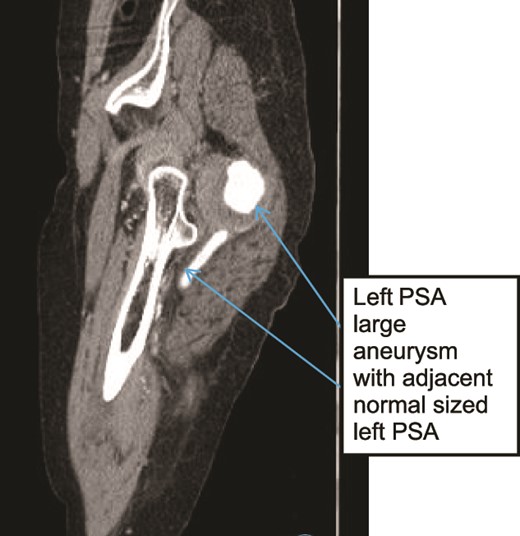

A 60-year old known psychiatric female patient presented with left LL pain and swelling for 1 week. She had claudication for 1 year and 4 months prior to presentation, she had fifth toe amputation after developing ulceration. On examination, all distal pulses were absent in the affected limb which was cold, with tender calf muscles and absent motor and sensory function. Patient was not cooperative for gluteal area examination. CTA showed bilateral prominent internal iliac arteries (IIAs), bilateral PSAs with left PSA fusiform aneurysm with surrounding thrombus, and no signs of rupture (Fig. 7) There was also central filling defect occluding the left mid-thigh PSA and left PA (Figs 8 and 9) With a diagnosis of Class III acute limb ischemia, the patient was offered surgical amputation but refused and was discharged against medical advice.

Case 3—sagittal images of LL CTA of the left LL arteries showing large aneurysm with surrounding thrombus with adjacent patent normal sized upper left PSA.